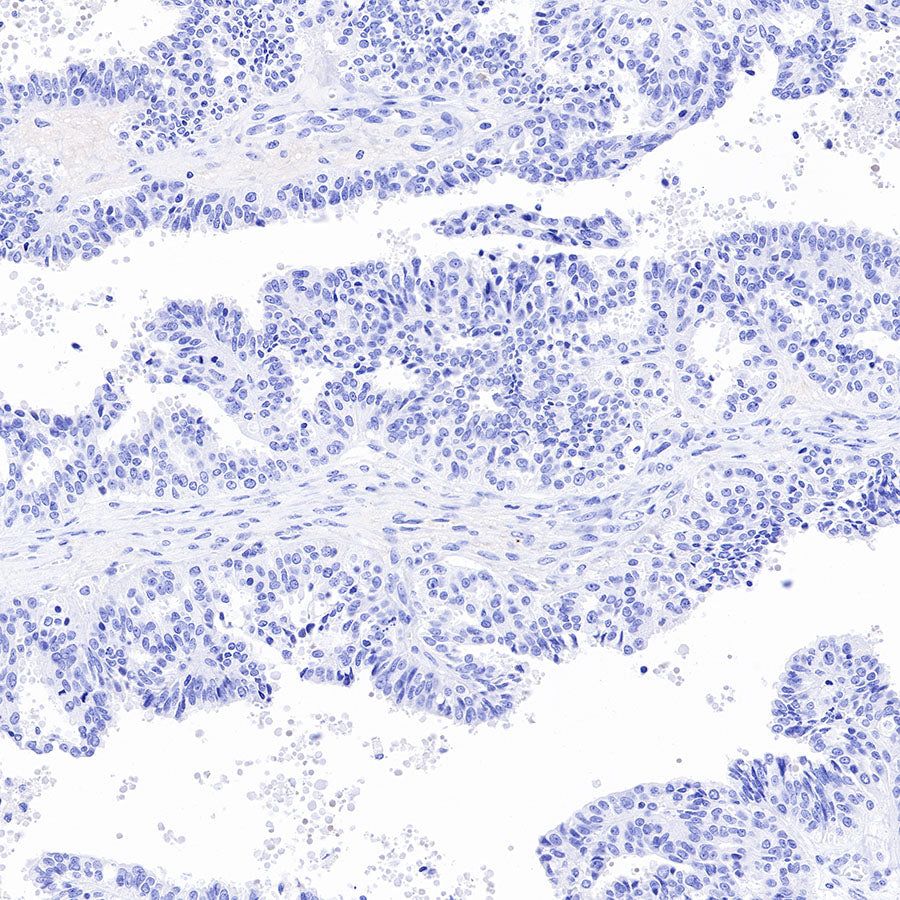

Immunohistochemistry

IHC shows positive staining in paraffin-embedded human prostatic hyperplasia. Anti-PSA antibody was used at 1/1000 dilution, followed by a HRP Polymer for Mouse & Rabbit IgG (ready to use). Counterstained with hematoxylin. Heat mediated antigen retrieval with Tris/EDTA buffer pH9.0 was performed before commencing with IHC staining protocol.

IHC shows positive staining in paraffin-embedded human prostate cancer. Anti-PSA antibody was used at 1/1000 dilution, followed by a HRP Polymer for Mouse & Rabbit IgG (ready to use). Counterstained with hematoxylin. Heat mediated antigen retrieval with Tris/EDTA buffer pH9.0 was performed before commencing with IHC staining protocol.

Negative control: IHC shows negative staining in paraffin-embedded human breast cancer. Anti-PSA antibody was used at 1/1000 dilution, followed by a HRP Polymer for Mouse & Rabbit IgG (ready to use). Counterstained with hematoxylin. Heat mediated antigen retrieval with Tris/EDTA buffer pH9.0 was performed before commencing with IHC staining protocol.

Negative control: IHC shows negative staining in paraffin-embedded human ovarian cancer. Anti-PSA antibody was used at 1/1000 dilution, followed by a HRP Polymer for Mouse & Rabbit IgG (ready to use). Counterstained with hematoxylin. Heat mediated antigen retrieval with Tris/EDTA buffer pH9.0 was performed before commencing with IHC staining protocol.